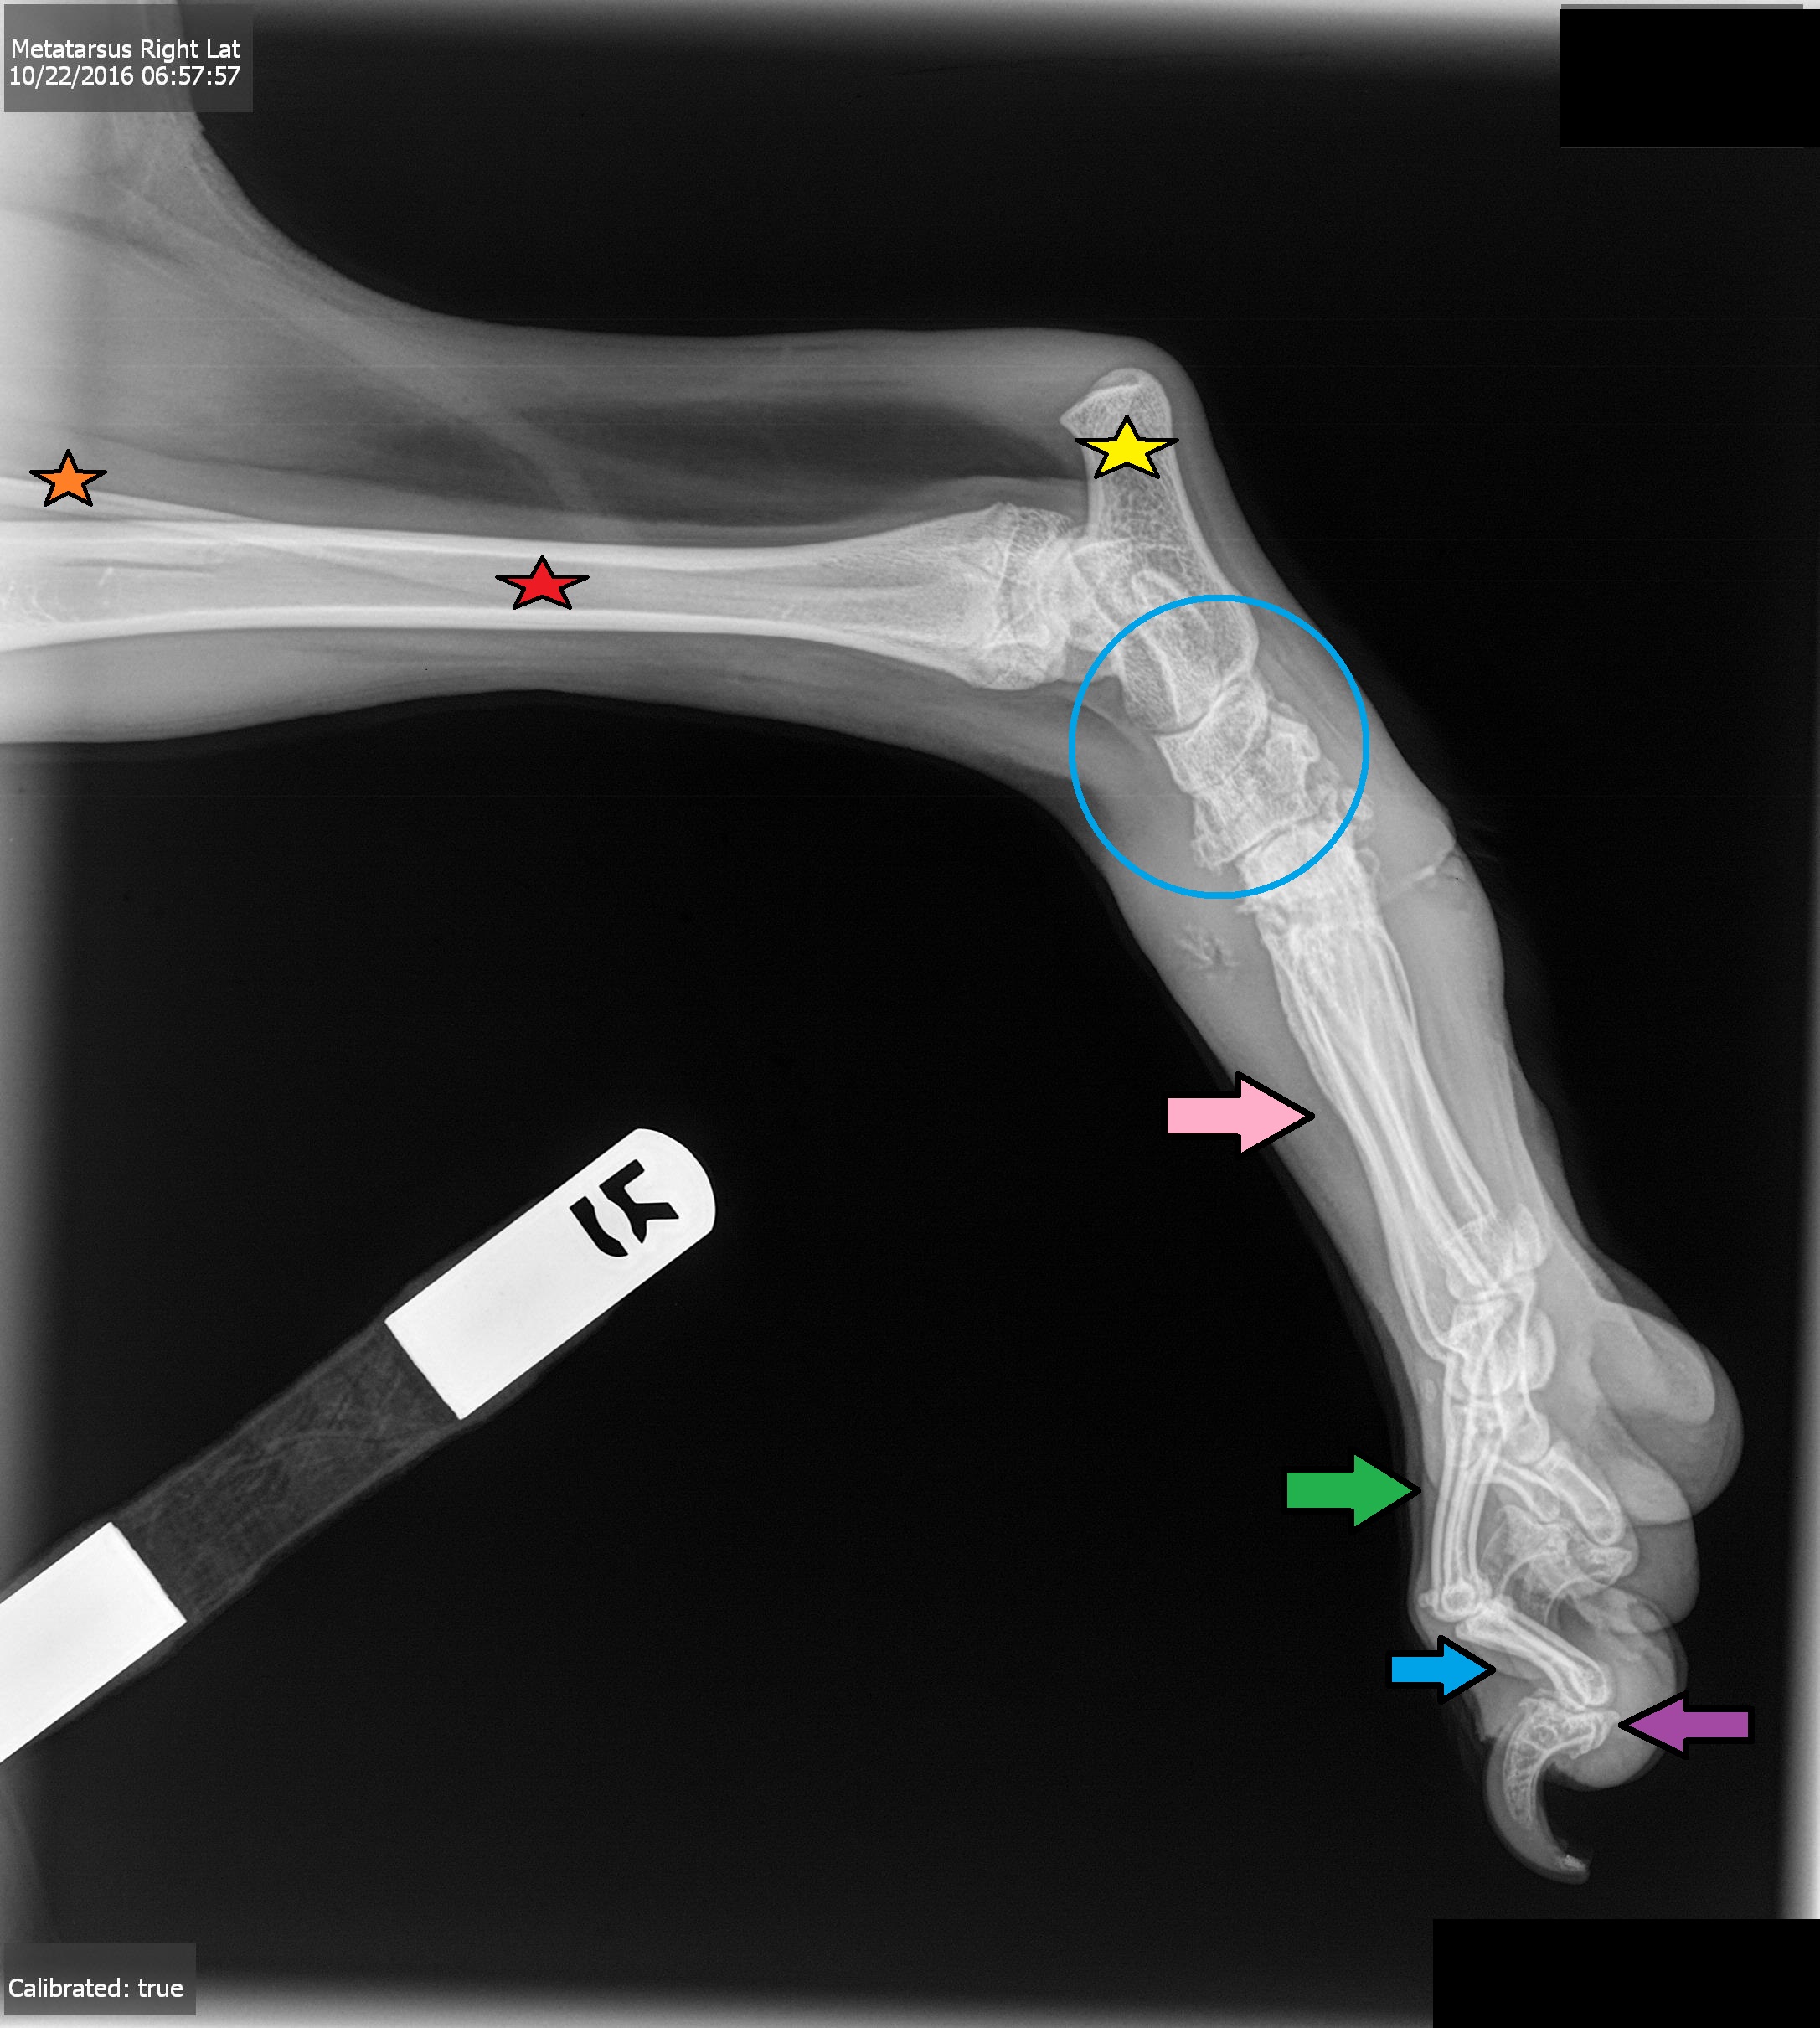

Orange Star

Fibula Bone

Red Star

Tibia Joint

Yellow Star

Calcaneal Process

Blue Circle

Tarsus Joint

Pink Arrow\

Metatarsal Bones

Green Arrow

Proximal Phalanges, P1

Blue Arrow

Middle Phalanges, P2

Purple Arrow

Distal Phalanges, P3